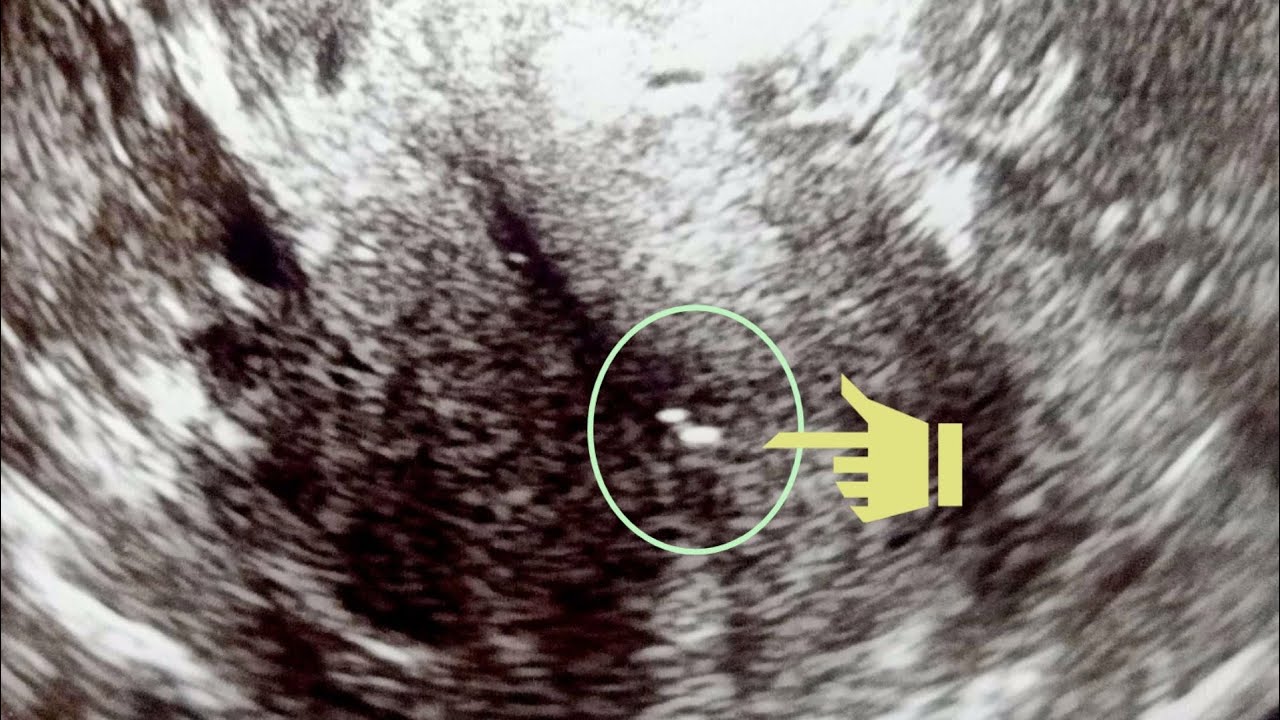

FET (Frozen Embryo Transfer) YouTube Frozen Embryo Transfer Day 9 a frozen embryo transfer (fet) is a procedure used in assisted reproductive technology (art) where a cryopreserved embryo. in your frozen embryo transfer timeline, a crucial step is the scheduled day for thawing your frozen embryos. Frozen embryo transfer success rates are determined by the age of the person providing the eggs. An embryo transfer is the final. Frozen Embryo Transfer Day 9.